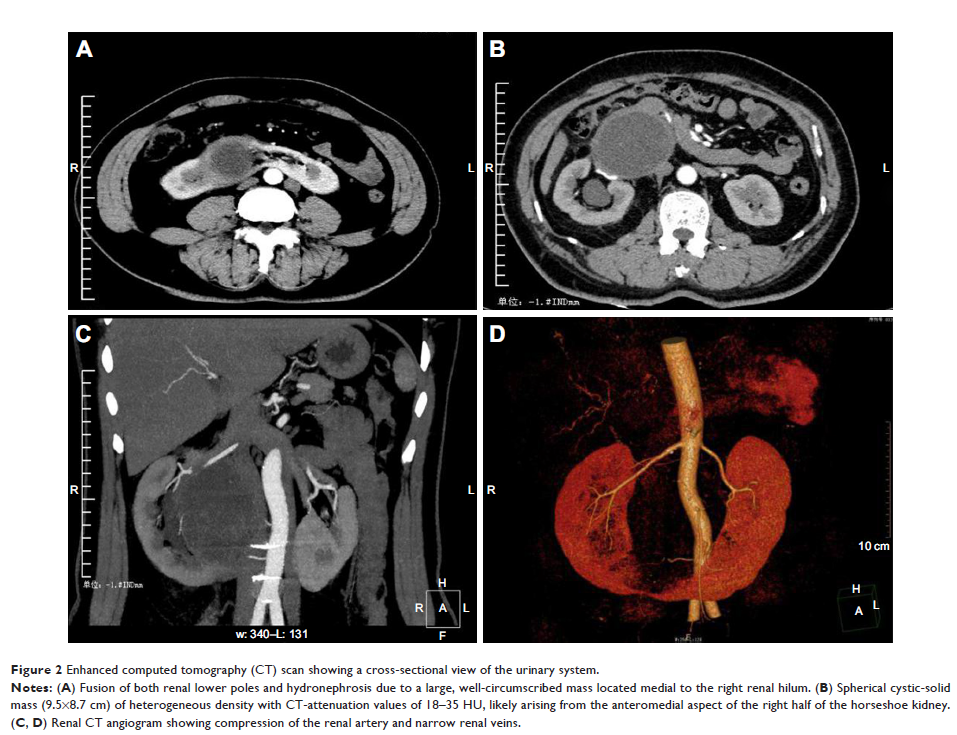

Case Report

- 作者:Xin Wang, Xiang Gao, Liang Wang, Zhihong Dai, Bo Fan, Haoyu Cui, Zhiyu Liu

- 期刊:OncoTargets and Therapy